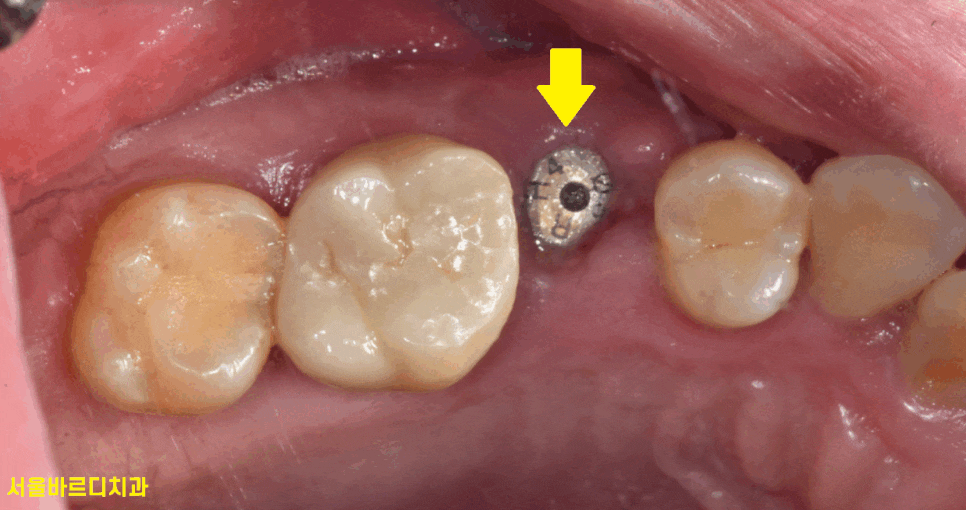

문제의 오른쪽 윗부분을 보는데..

딱 보입니다.

어금니 쪼개짐이 보입니다.

정확히 절반으로 어금니 쪼개짐

발생했습니다.

동그라미 구멍이 있는 치아가

풍산동 임플란트 한 부위입니다.

구멍이 있는 것은 추후 임플란트에 문제가 생겼을 때

수리하기위함인데

다음 포스팅에서 설명드리겠습니다.